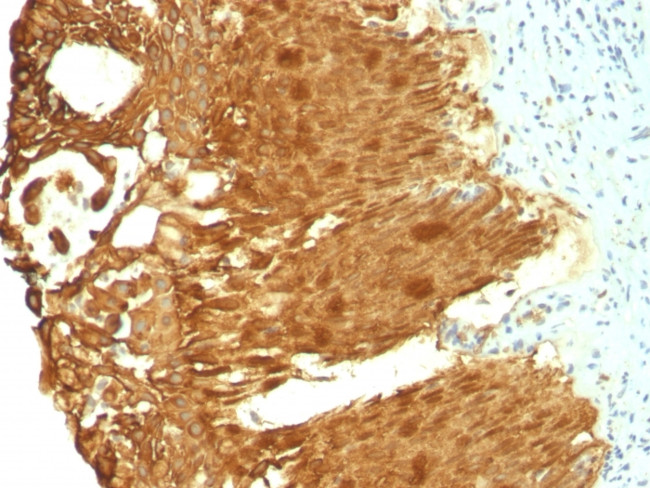

Cytokeratin 19 (KRT19) (Pancreatic Stem Cell Marker) Monoclonal Antibody (KRT19/799, KRT19/800)

Cytokeratin 19 is part of a subfamily of intermediate filament proteins and are characterized by a remarkable biochemical diversity, represented in human epithelial tissues by at least 20 different polypeptides. Cytokeratins range in molecular weight from 40-68 kDa and isoelectric pH between 4.9 - 7.8. The individual human cytokeratins are numbered 1 to 20. The various epithelia in the human body usually express cytokeratins which are not only characteristic of the type of epithelium, but also related to the degree of maturation or differentiation within an epithelium. Cytokeratin subtype expression patterns are used to an increasing extent in the distinction of different types of epithelial malignancies. The cytokeratin antibodies are not only of assistance in the differential diagnosis of tumors using immunohistochemistry on tissue sections, but are also a useful tool in cytopathology and flow cytometric assays. For example, cytokeratin 19 is not expressed in hepatocytes, therefore, it is useful in the identification of liver metastasis.